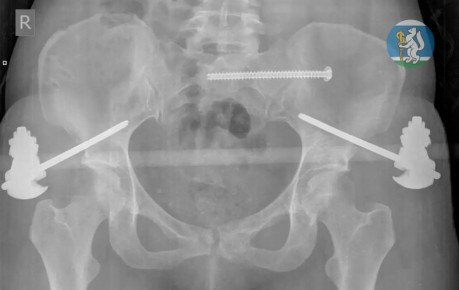

36-летняя жительница Екатеринбурга мыла окна на седьмом этаже и сорвалась вниз. С множественными переломами таза и позвоночника, открытыми переломами ног и тяжелой черепно-мозговой травмой ее доставили в Городскую...